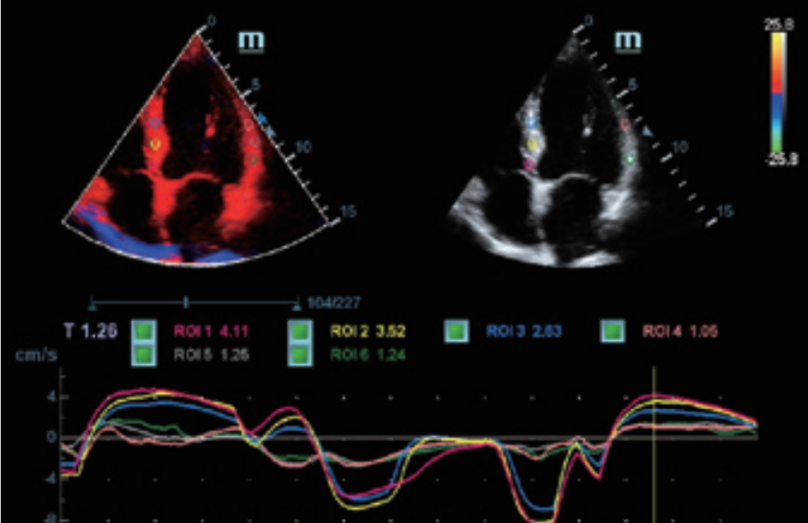

- Posee variadas herramientas que le permite al médico especialista realizar estudios de mejor calidad, como; iClear reducción de moteado, PSH imágenes por armónicos, iBeam formación de imágenes espaciales compuestas.